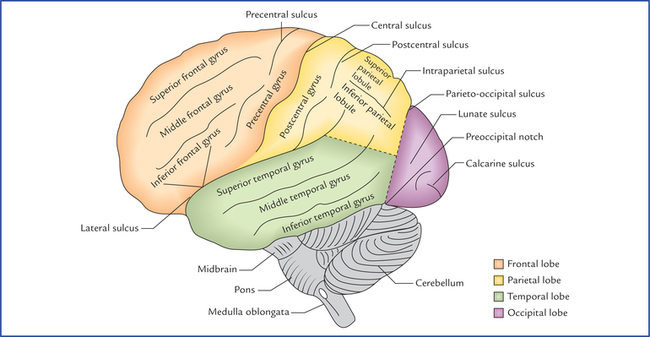

Супрамаргинальная извилина: Функции и Исследования